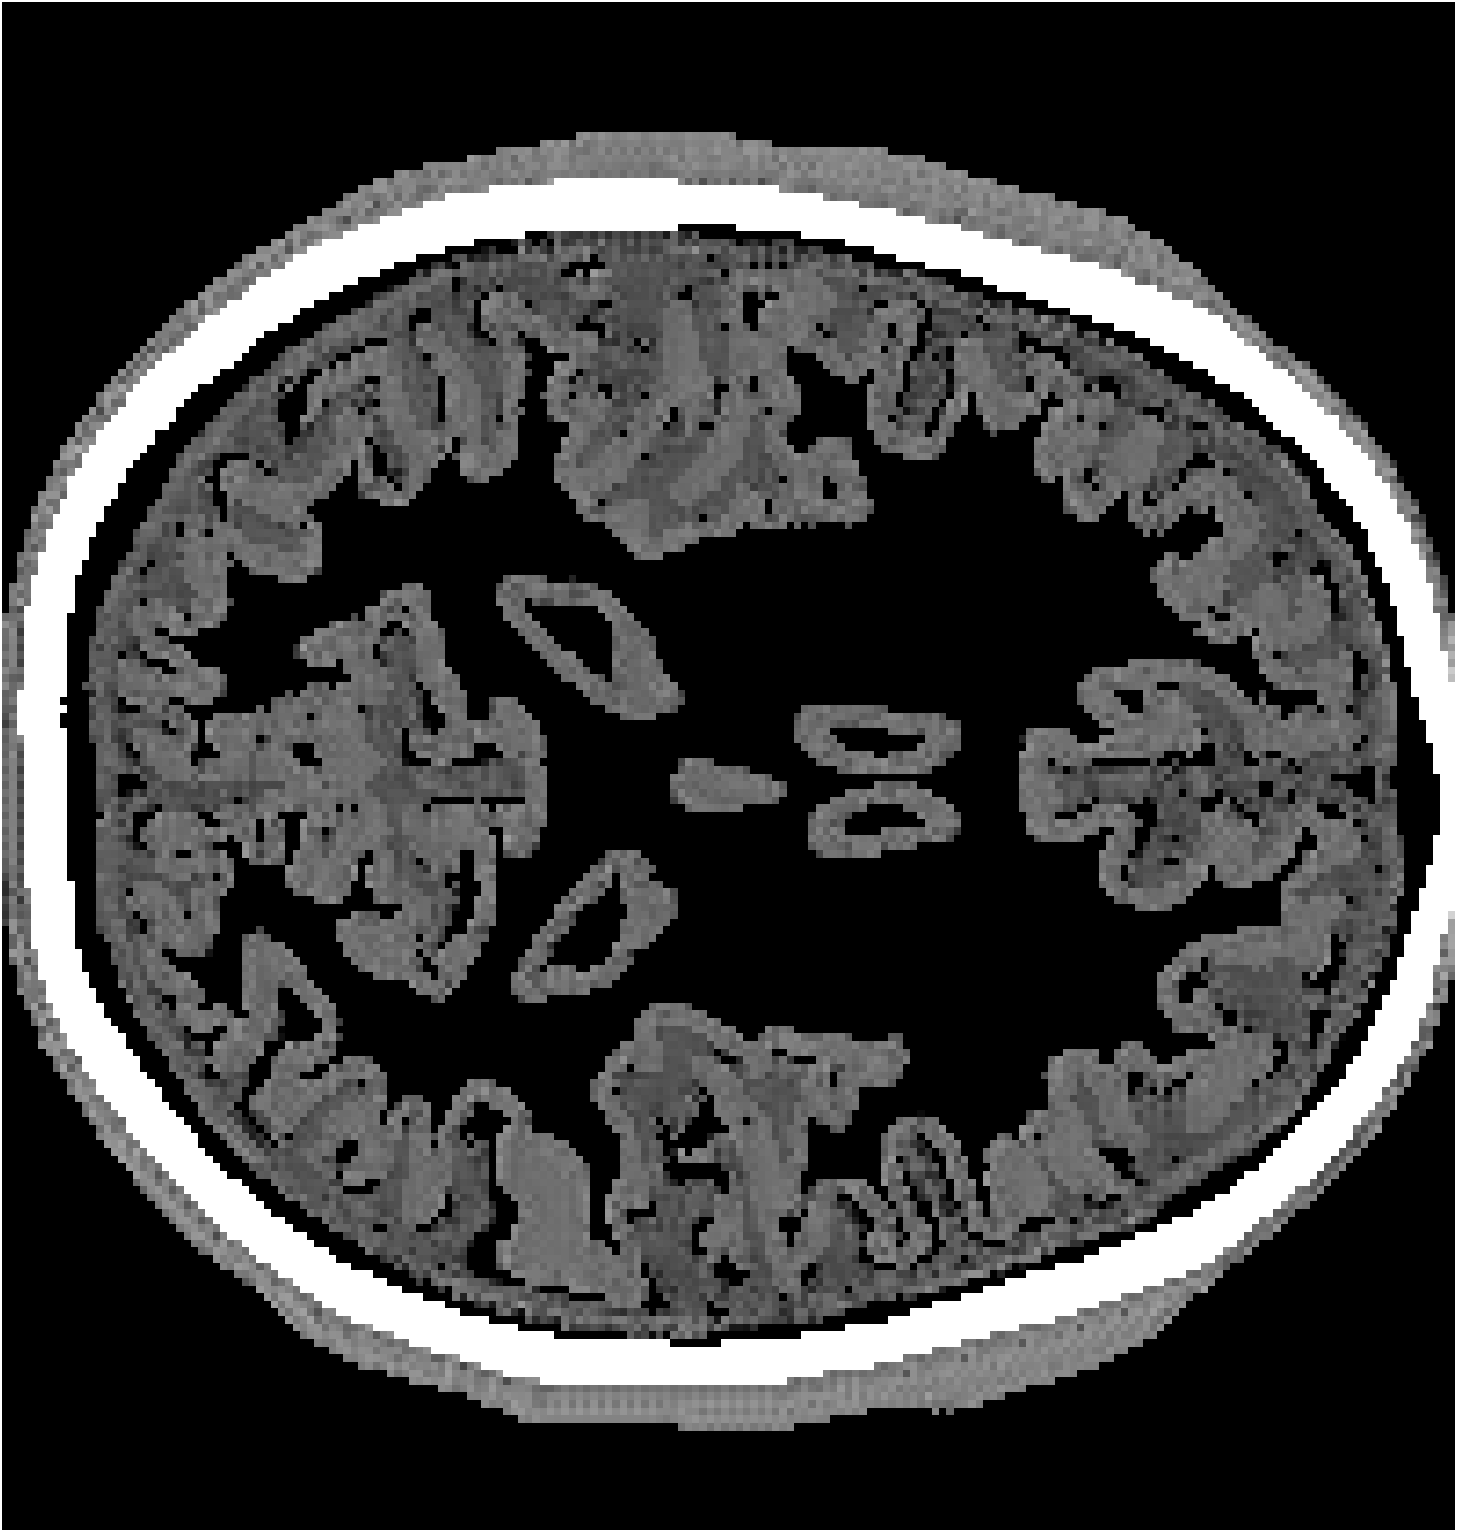

Figure 9: Comparison between physics-based FWI and the proposed BrainPuzzle reconstruction. (a) Homogeneous initial SoS; (b) FWI result using homogeneous initial model; (c) Smoothed initial SoS; (d) FWI result using smoothed initial model; (e) BrainPuzzle SoS reconstruction; (f) Ground truth. BrainPuzzle yields accurate and detailed structures even without a high-quality initial model.

Figure 10: Baseline comparison on partial-array data. Two axial slices: RCAN, LDM, ViT, and BrainPuzzle versus ground truth. BrainPuzzle preserves fine structure and boundary sharpness.

VI-B Test 1: BrainPuzzle Quantitative Performance Analysis

Table II summarizes the average performance over 50 slices of 2D brain images during the testing phase for both the full-transducer and partial-transducer datasets. The results demonstrate that the BrainPuzzle method outperforms all baseline models, achieving the highest SSIM values and the lowest RMSE values in both scenarios. Several key observations can be made: (1) We observe that the U-Net model and super-resolution baselines such as RCAN and CycleGAN achieve inferior performance compared to BrainPuzzle in terms of both SSIM and RMSE. These baseline models are less capable of handling the intricate spatial relationships and texture details required for accurate reconstruction, and thus struggle to effectively recover complete brain images. (2) BrainPuzzle also outperforms more advanced generative models, including LDM and ViT. While LDM and ViT exhibit more complex structures and training processes, they require significantly longer training and inference times compared to BrainPuzzle. Despite their complexity, these models fail to match the accuracy and efficiency achieved by BrainPuzzle, underscoring its robustness and practical applicability. (3) All models demonstrate significantly better performance on the full-transducer dataset compared to the partial-transducer dataset. This superiority is attributed to the clearer and more complete input brain fragments in the full-transducer scenario, which provide essential spatial information and finer-grained textures crucial for accurate reconstruction. In contrast, the partial-transducer data are not sufficient for high-quality reconstruction using limited and fragmented inputs.

The efficacy of the BrainPuzzle method is further demonstrated by the visual results presented in Fig. 10. These results showcase comprehensive brain images reconstructed across multiple 2D slices, highlighting the superior performance of the proposed method. A detailed analysis of these images reveals the following observations: (1) The RCAN baseline exhibits significant limitations in reconstructing the complete structural complexity of brain images. It struggles to capture the fine textures and intricate details characteristic of brain imagery, resulting in noticeably lower-quality reconstructions. (2) BrainPuzzle achieves a significant improvement in image quality, excelling in capturing finer details such as the accuracy of structural contours and the fidelity of textural patterns. These improvements can be particularly critical for medical diagnosis and analysis, where precision and detail play a pivotal role in ensuring reliable outcomes. (3) While LDM and ViT produce reasonably good results, they fall short of BrainPuzzle in accurately reconstructing smaller details. The minor deficiencies in their reconstructions highlight BrainPuzzle’s superior ability to preserve intricate features and deliver higher-quality outputs.

Additionally, we also compare BrainPuzzle with the physics-based FWI with results illustrated in Figure 9. The physics-based FWI is conducted using the steepest descent method over 30 epochs with the full-transducer dataset. We use two different initial models: one with a homogeneous velocity assigned to all tissues inside the skull (Figure 9(a)), and the other obtained by smoothing the ground-truth tissue distribution within the skull (Figure 9(b)). The model with a homogeneous initial condition produces poor results, while the one with a smoothed initial model yields much better outcomes, indicating that the physics-based method relies heavily on the accuracy of the initial guess of SoS. In contrast, Brain Puzzle SoS achieves good results even with the partial-transducer setup as shown in Figure 9(e).